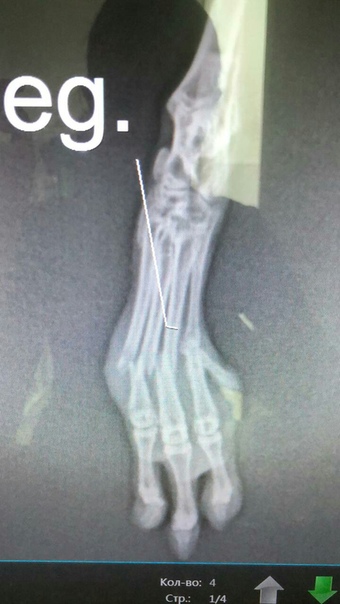

Chinchilla, 5 months, 320g, bone fracture of the metatarsus a week ago.

It's time to get the qualification of a microsurgeon ...